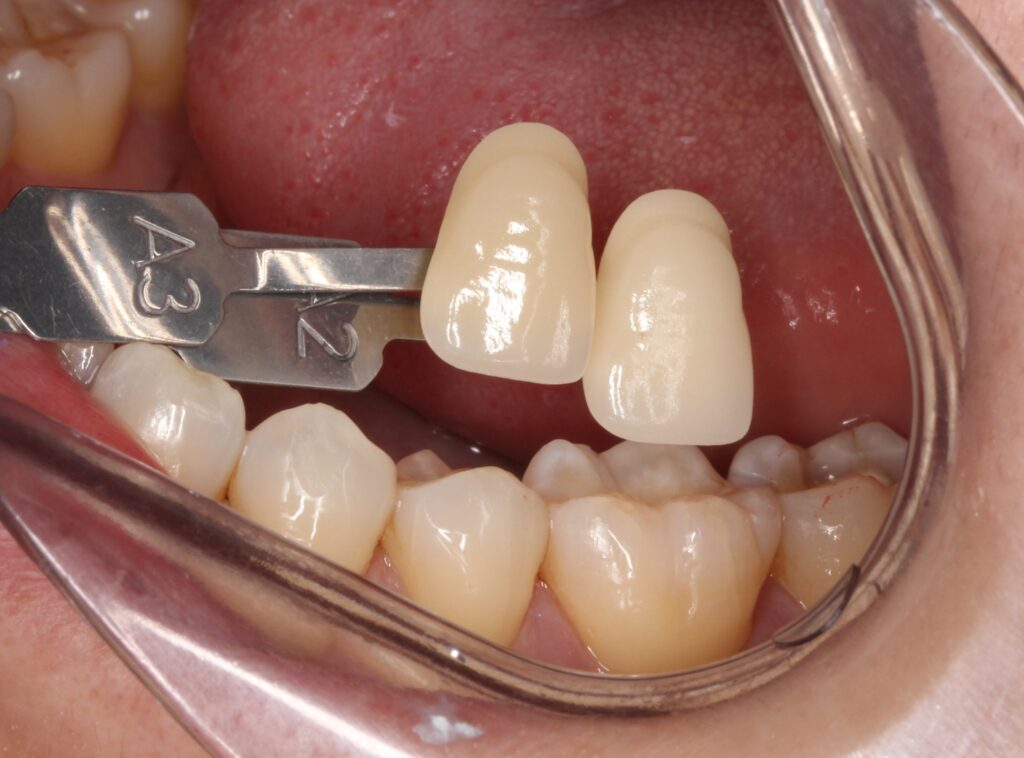

歯の色を写真を撮って合わせていきます。

歯科技工士がその方に合ったセラミックの歯を製作し、後日セラミックをセットします。